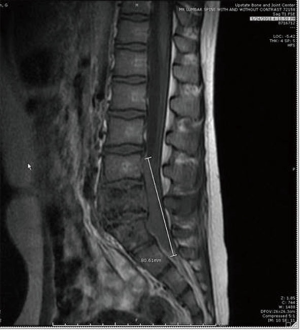

The present study describes a case of HL with initial extranodal osseous presentation in an 11-year-old male. The patient presented with 5 months of severe pain in the lumbar-sacral region with radiation to both lateral areas of the legs, without any substantial neurological deficits, fever or weight loss. Red blood cell count was normal, and further examination revealed cervical lymphadenopathy. Radiological evaluation detected a lytic lesion in L5 vertebral body and right iliac bone, extending to both psoas muscles (Figure 1). Pathological evaluation included biopsy of the L5 lesion (Figure 2) which showed a prominent vascular component, scattered Reed-Sternberger (RS) cells with prominent nucleoli, and a heavy eosinophilic infiltrate. The staging bone marrow biopsy showed involvement by HL (Figure 3).